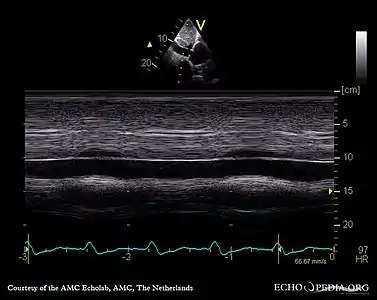

Echocardiography

If pulmonary hypertension is suspected based on the above assessments, echocardiography is performed as the next step.[10][11][53] A meta-analysis of Doppler echocardiography for predicting the results of right heart catheterization reported a sensitivity and specificity of 88% and 56%, respectively.[55] Thus, Doppler echocardiography can suggest the presence of pulmonary hypertension, but right heart catherization (described below) remains the gold standard for diagnosis of PAH.[10][11] Echocardiography can also help to detect congenital heart disease as a cause of pulmonary hypertension.[10]

- 4 month old with pulmonary hypertension as seen on ultrasound[56]

4 month old with pulmonary hypertension as seen on ultrasound[56]- Long standing pulmonary hypertension[57]